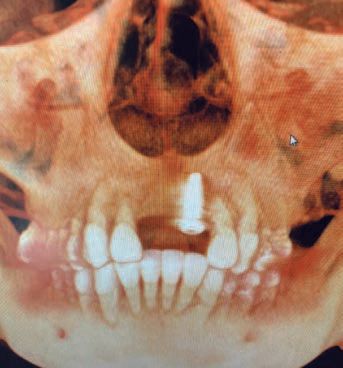

After taking a CAT screen Dr. Mark noticed that #9 was not placed in bone but was free floating in the soft tissue (Figures: A, B) and it too would fail. The patient informed Dr. Mark that she was told that she would need more bone grafting followed by another six months of waiting before new implants could be placed by the original dentist. Commenting on the proposed treatment plan, Dr. Mark said: “Upon examination of the patient and detailed review of the 3D anatomy of the anterior region of the maxilla, I concluded that a ridge splitting technique would be the best option moving forward.” He went on to inform the patient that if the ridge spitting was successful, he would be able to place the implants at the same time. The patient agreed to the procedure and was amazed that the entire process could be completed in one visit.